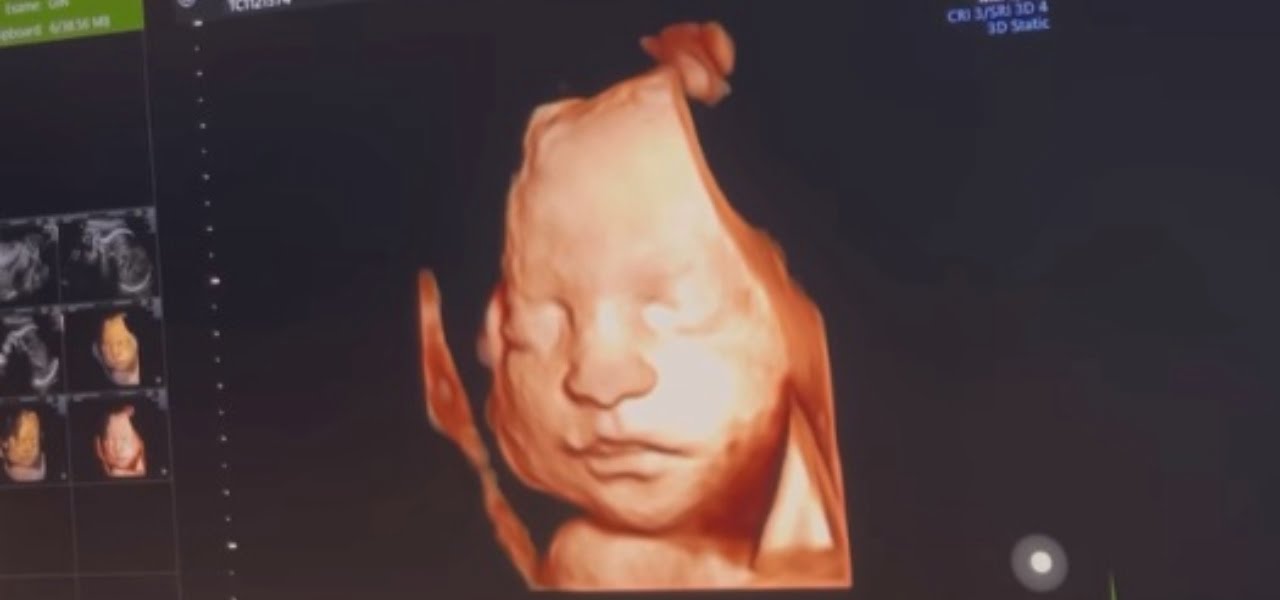

Georgette Polizzi ha pubblicato il video dell’ecografia della figlia. L’ex concorrente di Temptation Island e il marito Davide Tresse aspettano una bambina che si chiamerà Sole e che nascerà a marzo. Georgette non trattiene l’emozione e, a corredo del video, scrive: “Ieri sera sono riuscita a vederla con l’ecografia 3D durante la visita e con la voce rotta dall’emozione non riuscivo a smettere di dire quanto è bella! Sole fortunatamente sta benissimo, cresce a vista d’occhio e ieri ci ha pure fatto un sorriso! È incredibile pensare che tra poche settimane sarà tra le nostre braccia, potremo finalmente toccare il nostro sogno”.

Georgette ha aggiunto che il primo dettaglio che non è passato inosservato sono state le labbra della piccola e ha rivelato: “Ho passato tutta la serata di ieri a studiarla, a guardare e riguardare video e foto dell’ecografia scoprendo ogni volta un dettaglio nuovo del suo visino. La prima cosa che ho notato sono state le sue labbra! Pensavo le avesse prese da me… e invece ha il becchetto del Momo! Le stesse labbra che per anni ho amato alla follia…e che ora ha anche la nostra bambina! Guardate il momo da piccolo quanto le somiglia. Che spettacolo la vita”. Nel video, si sente in sottofondo Georgette Polizzi che commenta le immagini che appaiono sullo schermo: “È tutta mio marito”. Infatti, Georgette ha poi aggiunto delle foto che ritraggono il marito, a dimostrazione che la somiglianza con la figlia che deve nascere è davvero incredibile.